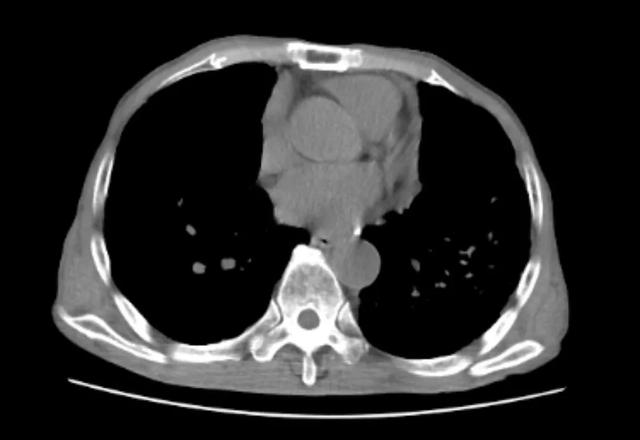

「是否需要进行肺移植手术,还是需要经过医生专业评估,结合患者自身身体状况,来最终决定的。」杨莉主任表示,经过入院胸部 CT 检查,可见陈大爷肺内多发由于粉尘沉积引起的肺部肿块,融合成团,如同白色水泥团块一样,紧紧地附着在患者两处肺门的地方,初步诊断矽肺。

陈大爷的 CT 报告